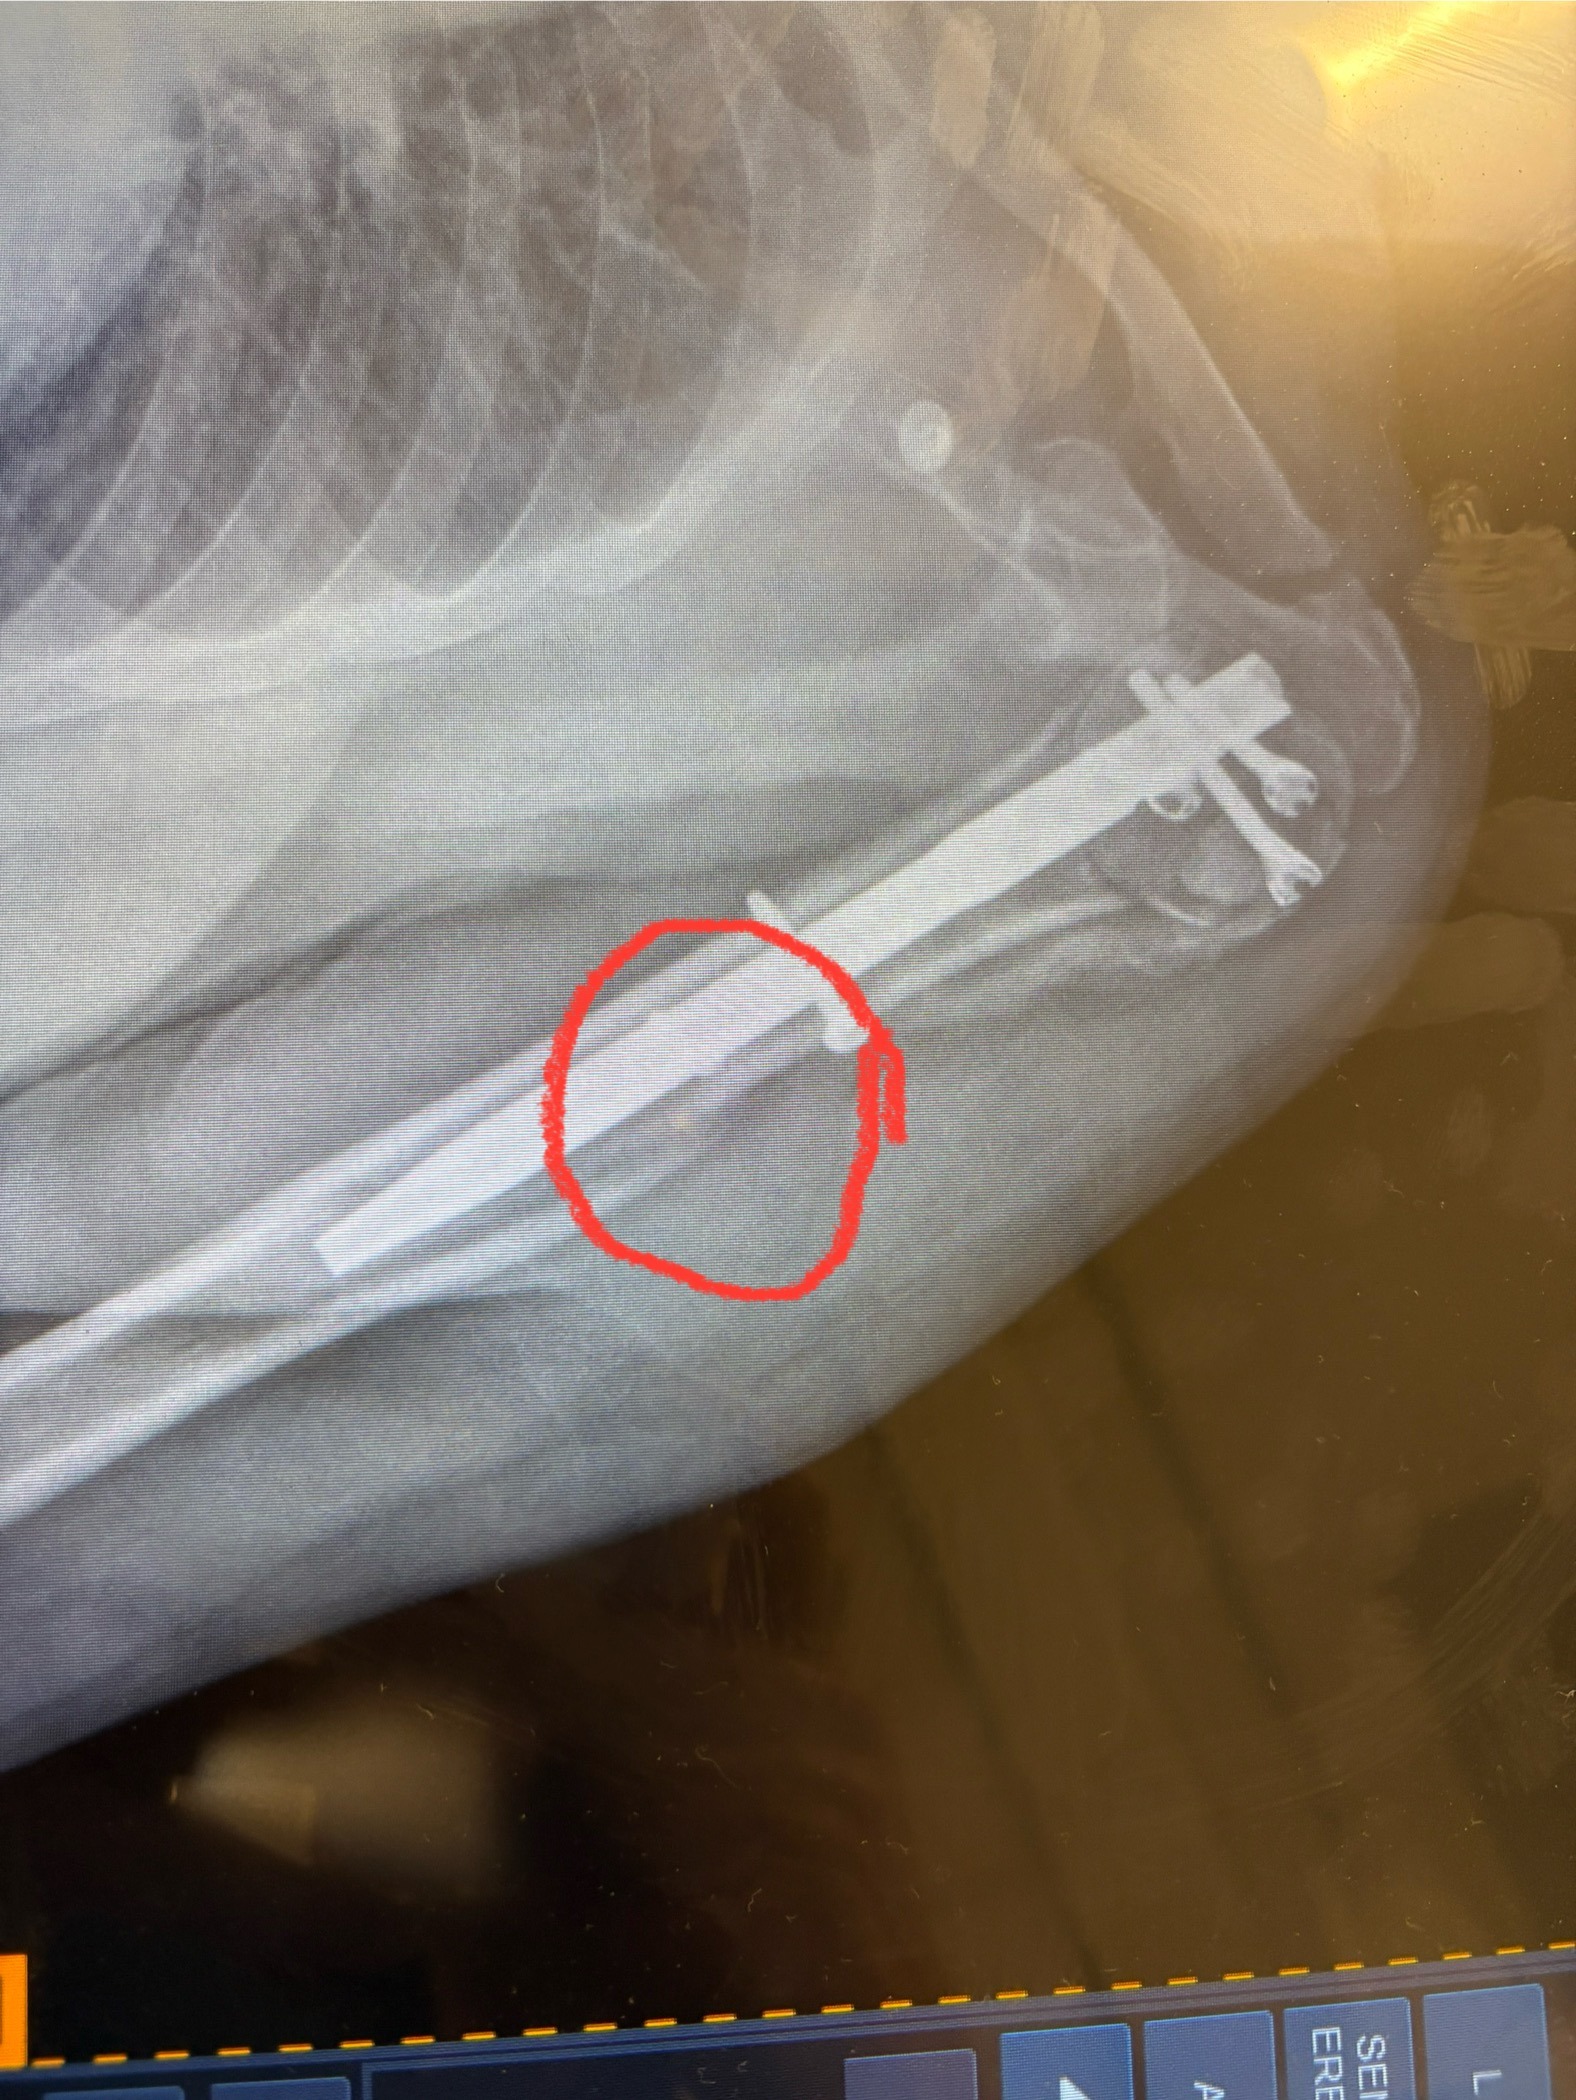

Hi Friends, this is Rene Battistone. I'm reaching out to all the friends and clients of Scott Smith. As most of you know, Scott took a serious fall on September 16th. He crushed his left shoulder and needed immediate surgery. Because of his previous conditions, the surgery was complicated, and he was at St. Mary's Hospital for 3 weeks (including during his 60th birthday!) before he could actually stand, walk, and go up a few stairs. He's home now, but recovery has been slow. He got the news at his follow-up visit that he may need a second surgery since the shoulder is not healing well. This, unfortunately, is delaying physical therapy too. Scott needs help with his rent and bills until he can get back to work. Please donate what you can and just as importantly, please share this post with your network.